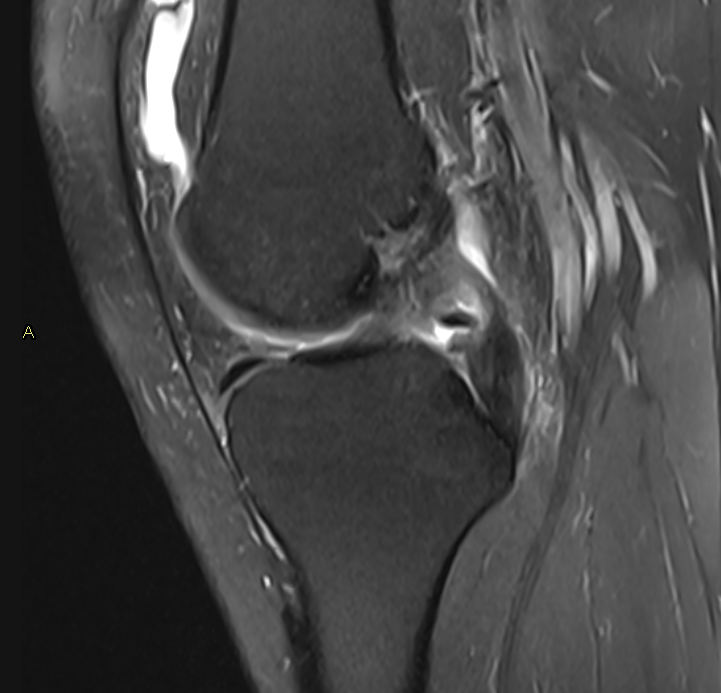

3. Posterior Cruciate Ligament (PCL) tear